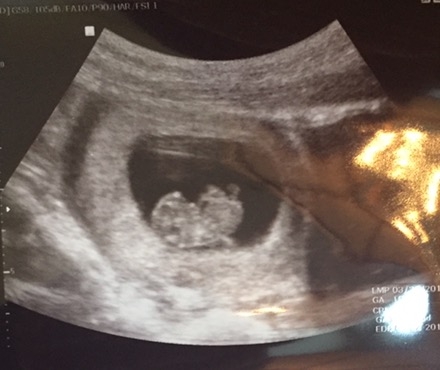

Baby at 9 weeks. Measuring right on track and a healthy heartbeat. Baby was wiggly during the ultrasound.